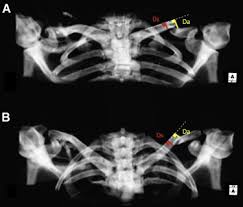

Clavicle X Ray Positioning : Shoulder Clavicle Scapula Youtube - Positioning the catheter tip too proximally, for example in the right or left brachiocephalic veins, is associated with increased risk of line infection and thrombosis.. 10 x 12 crosswise 2. In this position, the image will clearly show the condition of the. Additional imaging of the lung apices • properly positioned (not rotated or angulated): Standardized clavicle radiographs were obtained in both supine and upright positions for each patient. 10 x 12 film crosswise 2.

Digit imaging requires diligent positioning. Please remove all obscuring objects and, as always, practice proper radiation protection. Trace the line under the clavicle towards the svc. Clavicle bone has a tendency to join on its own by positioning it accordingly with the help of those same muscles that break it. 10 x 12 crosswise 2. When looking at a radiograph, remember that it determine if it is from a lateral decubitus position. Positioning the catheter tip too proximally, for example in the right or left brachiocephalic veins, is associated with increased risk of line infection and thrombosis. Standardized clavicle radiographs were obtained in both supine and upright positions for each patient. Patient positioning techniques for a lower. The position of the patient should be either upright or supine. Boning up on humerus, clavicle, and ac joint positioning. Boning up on humerus, clavicle, and ac joint positioning. In addition to covering anteroposterior and lateral radiographs, dr.

10 x 12 film crosswise 2. The upright position may be more comfortable than the table for some patients. Getting the most from shoulder positioning. Xray examination of the clavicle radiography of clavicle is routinely done in radiology department in both ap and ap axial projection. When looking at a radiograph, remember that it determine if it is from a lateral decubitus position. Bones • sternum • clavicles • scapulae • ribs • spine. In this position, the image will clearly show the condition of the. Boning up on humerus, clavicle, and ac joint positioning. In addition to covering anteroposterior and lateral radiographs, dr. Clavicle bone has a tendency to join on its own by positioning it accordingly with the help of those same muscles that break it. The position of the patient should be either upright or supine. Hand, thumb, fingers, wrist, forearm, elbow, humerus, shoulder and clavicle. Boning up on humerus, clavicle, and ac joint positioning.